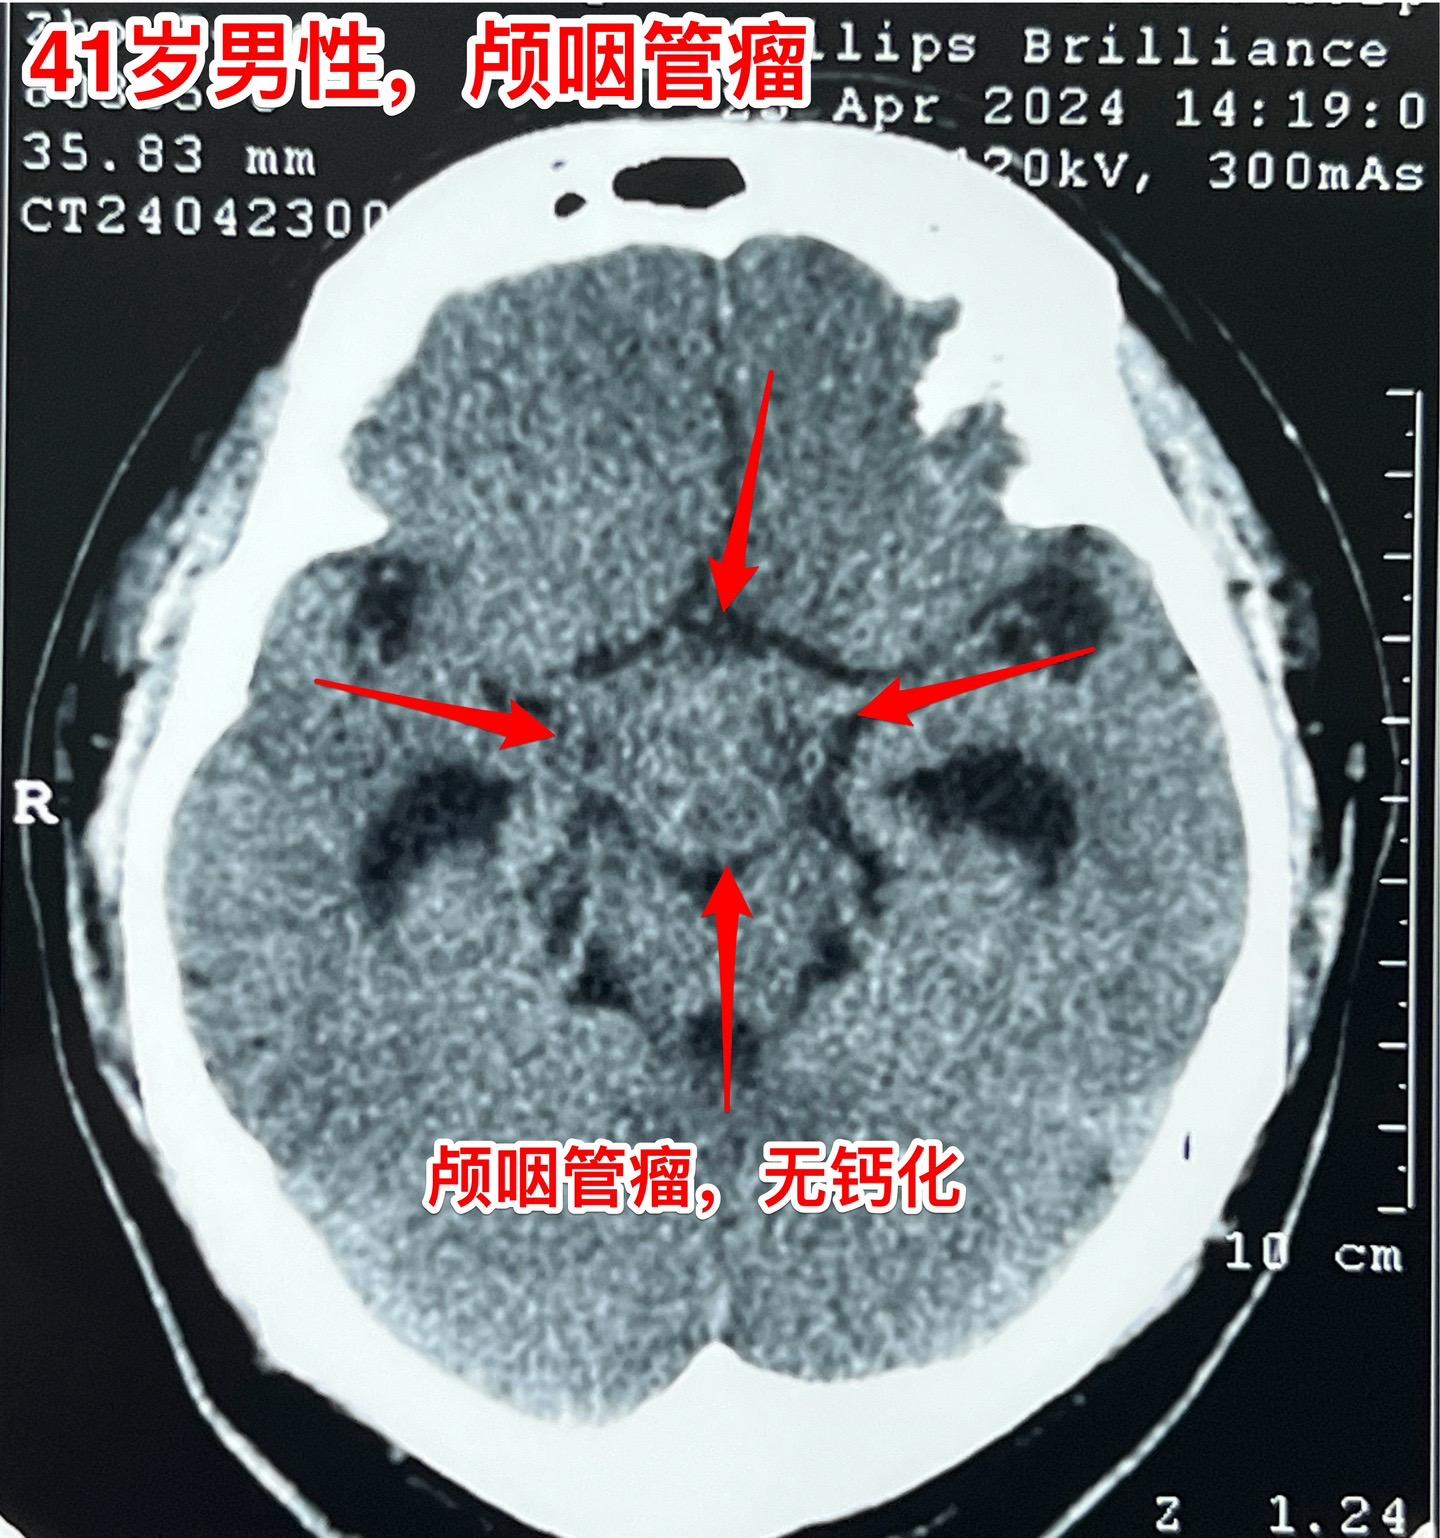

三个月颅咽管瘤直径增加了1厘米。41岁辽宁省沈阳的男性,五个月前因眼前发花到医院检查发现颅咽管瘤,同时期他的一个吉林省的朋友也发现患有颅咽管瘤(吉林省朋友的颅咽管瘤有钙化,2024.1.25在我科作了手术)(沈阳病人的颅咽管瘤没有钙化)。 惧怕手术是人之常情。沈阳患者发现颅咽管瘤后也是害怕作手术的,所以他选择试试中药治疗,到成都某医院去看病,服用中药三个月,到2024年4月复查磁共振显示肿瘤的直径长大了1厘米,同时视力症状也越来越明显,化验激素也出现下降。所以患者就下决心来找我作手术。